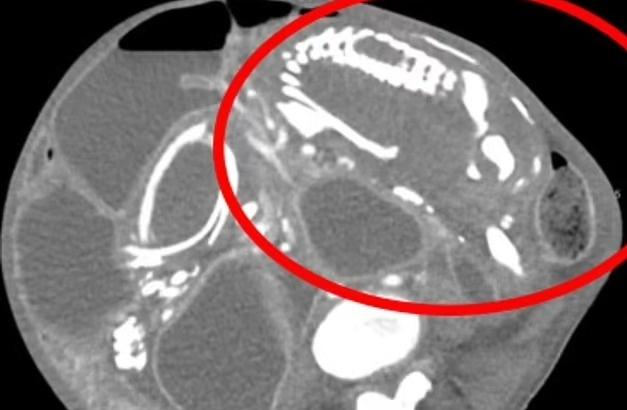

Из черепа годовалой девочки извлекли ее недоразвитого близнеца (18+)

Годовалая девочка поступила к врачам в Китае с аномально крупной головой и "когнитивными проблемами". Выяснилось, что внутри ее головы находятся останки крошечного младенца, вероятно ее близнеца. Такое медицинское состояние, называемое "фетус ин фету" (зародыш в зародыше), чрезвычайно редкое, а уж когда плод находится внутри головы, и вовсе почти невероятный случай, за всю историю таких известно […]